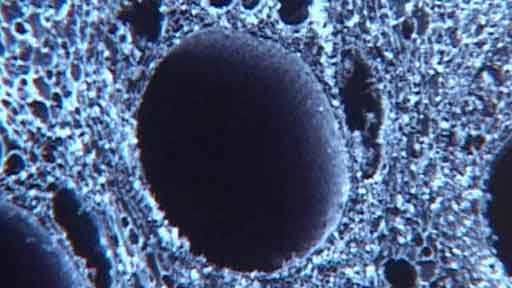

Infatti, è stato scoperto che a livello microscopico la struttura di alcuni legni è molto simile a quella del tessuto osseo. Inoltre, la struttura condivide proprietà biomeccaniche quali un’elevata resistenza e leggerezza, grazie alla sua organizzazione gerarchica.

Il processo di trasformare il legno in impianti comporta il trattamento termico del legno per rimuovere la cellulosa, la lignina e altri materiali vegetali. Ciò lascia uno scheletro di carbonio che può essere infiltrato e fatto reagire con il calcio, l’ossigeno e il fosfato per ottenere un materiale poroso che a sua volta può chimicamente e meccanicamente imitare il tessuto osseo.